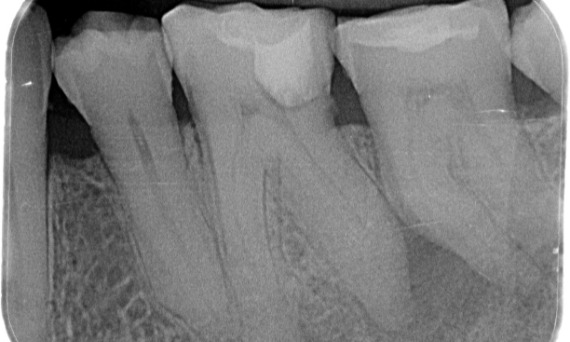

After: Access cavity was done as conservative as possible. TruNatomy was the system of choice due to the young patient’s age. We needed to preserve dentine as much as possible to increase the tooth ability to overcome occlusal load and increase the longevity of the final restoration.